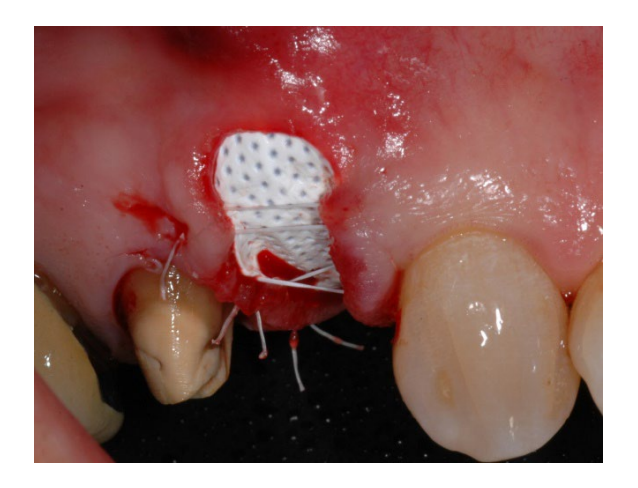

In group A, socket preservation with intentionally exposed non-resorbable d-PTFE membrane (test group, Figures 1–4), the residual alveolar socket was grafted with porcine-derived cancellous anorganic bone material (0.25–1 mm particles, Zcore, DeOre s.r.l., Negrar [Vr], Italy). Then, a non-resorbable, dense-polytetrafluoroethylene (d-PTFE) membrane (Cytoplast TXT1224, DeOre) was shaped according to the dimension of the residual socket, and it was inserted into a buccal and lingual pocket. Finally, a horizontal mattress suture (Cytoplast PTFE Suture 4-0, DeOre) was placed to secure the membrane and stabilize it to the soft tissue margins. The application of the non-resorbable d-PTFE membrane did not require primary closure via buccal flap advancement. The sutures were removed between 10 and 14 days post-surgery, and the non-resorbable d-PTFE membrane was removed between the fourth and the fifth weeks after surgery. After that, the wound was left to heal for about five months, allowing by the process of re-epithelialization.